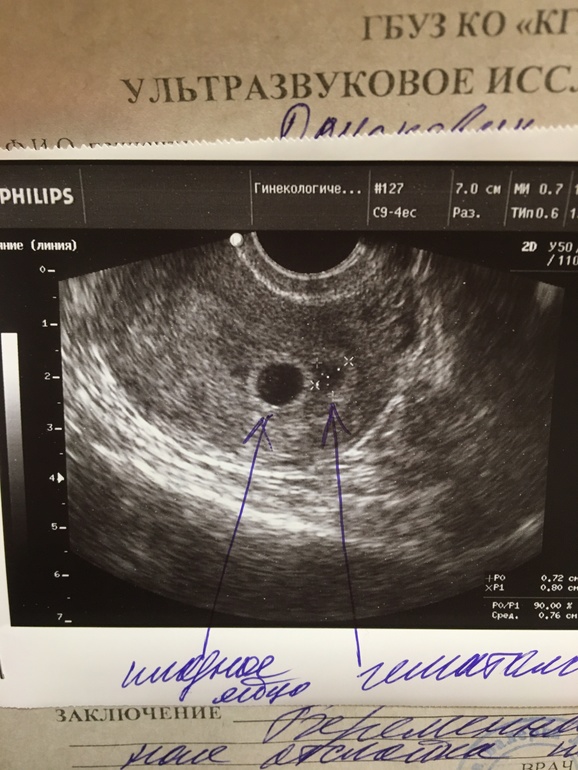

Девочки, всем привет) две недели назад ходила на узи, для подтверждения маточной беременности. Нашли ПЯ, эмбрион не увидели, по узи 4-5нед., по М 7нед было и гематому 7,5х8мм...гинеколог сказала повторить узи через две недели, чтобы найти эмбриона и сердечко. Сегодня делала узи, эмбрион и сердечко есть, срок по узи поставили 9нед., по М 9,2 !!!но гематома увеличилась тоже 18х8мм...ставила свечи утрожестан, сейчас дозу увеличили...надеялась что гематома уменьшится, а она наоборот растёт...у кого подобные случаи были, интересно послушать вас. Фото в коментариях

А почему она сразу вас не направила к гинекологу?? У меня как на узи нашли гематому сразу отправли к гинекологу, а та положила в стационар, гематома опасная штука. Во первых при не лечении она будет расти, во вторых если вдруг начнёт выходить может потянуть за собой плодное яйцо, а это черевато последствиями выкидыша. Вы что бегом в больницу, темболее она у вас рядом с плодом!!!

И утрожестан вам не помощник с гематомой, он укрепляет плод и стенки плодного яйца, а уж на гематому ни как не влияет

У гинеколога я была и это она увеличила дозу...сейчас вообще нет возможности лечь в стационар, хотя я бы давно лежала там с удовольствием. Двое детей маленьких и оставить не с кем сейчас...жду 10 декабря, у мужа отпуск будет, тогда может и лягу